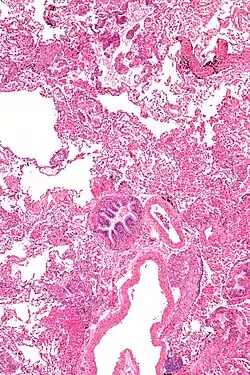

La destrucción pulmonar en LAM es una consecuencia de la infiltración difusa por células neoplásicas similares al músculo liso que invaden todas las estructuras pulmonares, incluidos los vasos linfáticos, las paredes de las vías respiratorias, los vasos sanguíneos y los espacios intersticiales.[13] Las consecuencias de la obstrucción de los vasos y las vías respiratorias incluyen acumulaciones de líquido quiloso, hemoptisis, obstrucción del flujo aéreo y neumotórax. El curso típico de la enfermedad muestra disnea progresiva con el esfuerzo, espaciada por neumotórax recurrentes y, en algunos pacientes, derrames pleurales quilosos o ascitis.[14]